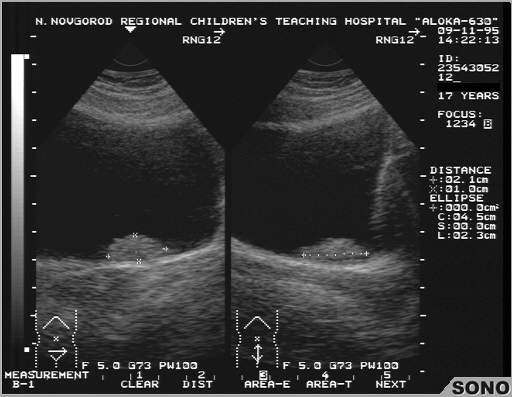

- ультразвуковое исследование мочевого пузыря на предмет величины образования, места его локализации и строения;